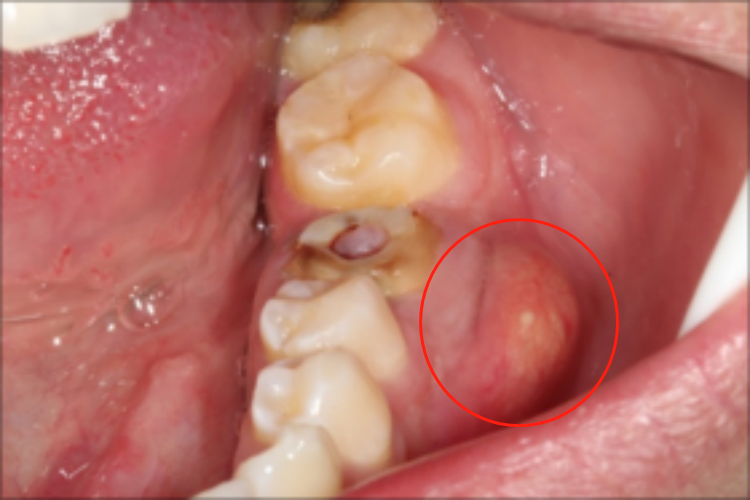

牙周脓肿

有较深的牙周袋,而患牙一般无龋,牙髓多有活力,脓肿一般局限于牙周袋壁较近的龈缘,疼痛相对较轻,牙齿的松动明显,消肿后仍然松动,叩痛相对较轻而侧向叩痛明显,病程相对较短。